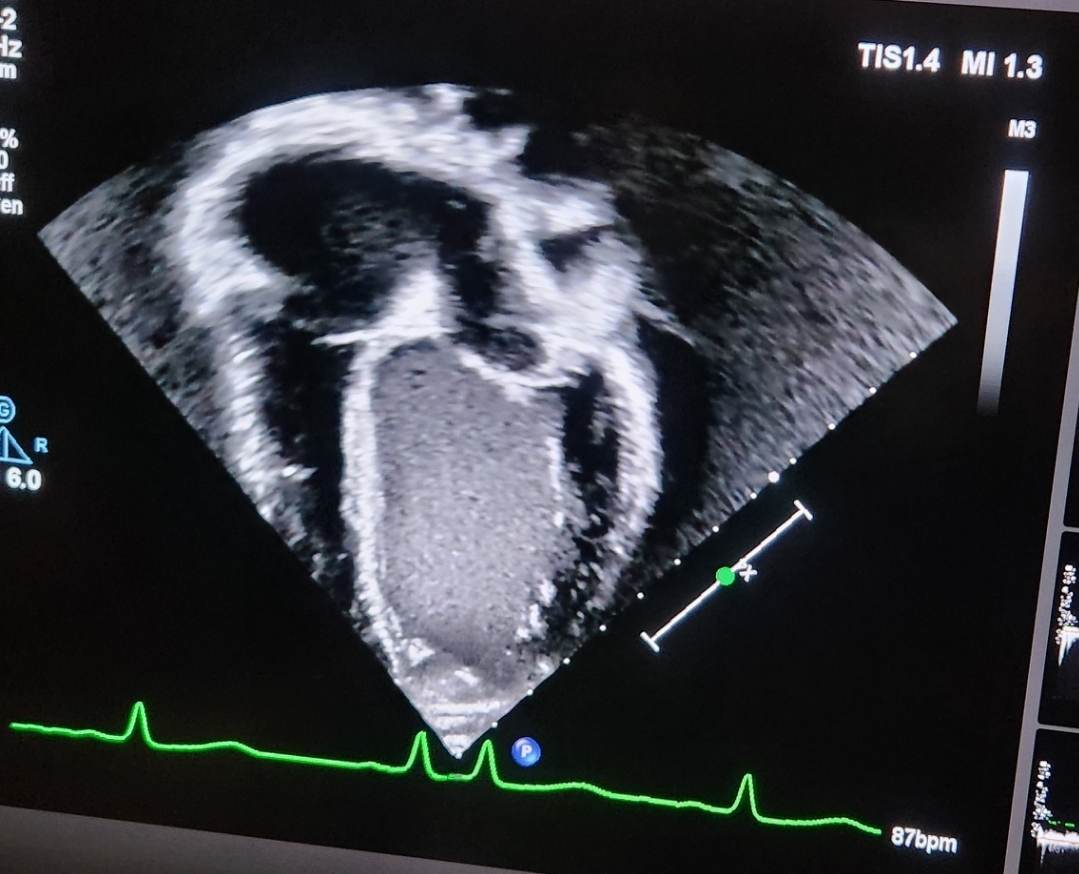

Which brings us to today’s Echo. We are 6 weeks from those Unicorn dates for surgery and her team at Seattle decided a quick check was in order after all the illness.

This photo illustrates exactly what can’t be put into words. A heart that is enlarged and struggling. Her LV is enormous compared to the rest of her heart. Luckily it’s only slightly worse than the end of February. Her function is stable and that’s a great thing.